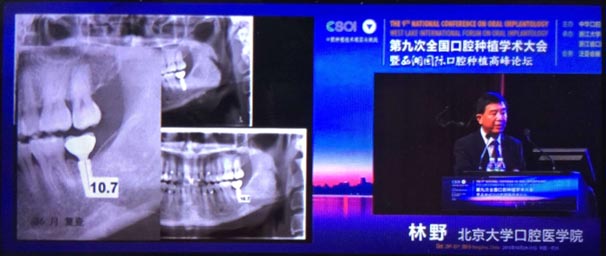

20151029日第九次全國(guó)口腔種植學(xué)術(shù)大會(huì)暨西湖國(guó)際口腔種植高峰論壇在浙江省人民大會(huì)堂隆重開(kāi)幕。這是中華口腔種植專業(yè)委員會(huì)主辦的兩年一度的全國(guó)性學(xué)術(shù)會(huì)議,代表了中國(guó)口腔種植學(xué)發(fā)展的水平和方向。

會(huì)議期間國(guó)內(nèi)知名口腔專家針對(duì)當(dāng)前口腔種植領(lǐng)域熱點(diǎn)進(jìn)行了精彩的學(xué)術(shù)演講。其中北京大學(xué)口腔醫(yī)學(xué)院林野教授的演講主題是種植體設(shè)計(jì)及臨床意義。

威高演講中林野教授對(duì)國(guó)產(chǎn)品牌WEGO牙種植體系統(tǒng)的設(shè)計(jì)和臨床表現(xiàn)表示肯定,向在座觀眾展示了WEGO牙種植體系統(tǒng)的臨床病例。病例對(duì)76WEGO牙種植體進(jìn)行了平均21個(gè)月的追蹤觀察,結(jié)果表明WEGO牙種植體脫落、松動(dòng)、種植體周?chē)‖F(xiàn)象均為0,頸部骨吸收平均值為0.20mmSD0.07。